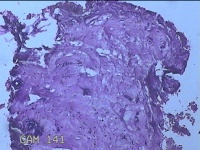

性别

女

年龄

27岁

临床诊断

乳腺脓肿

一般病史

发现右侧乳腺脓肿1个月余,伴局部疼痛不适。

标本名称

右侧乳头下方结节

大体所见

灰白暗红色结节0.8x0.5x0.3cm一个,表面糜烂。

组织没固定好